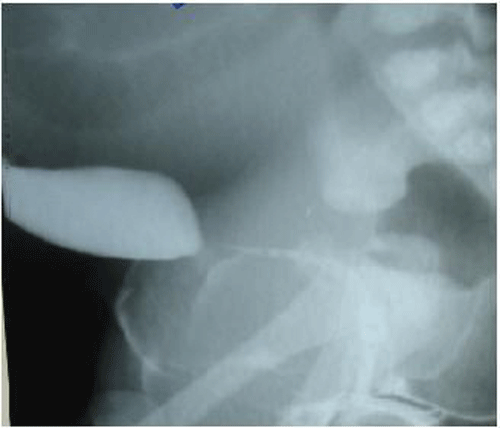

A large abdominal mass displacing the bowel to upper abdomen was seen on plain abdominal radiograph. Ultrasound and CT scan findings (Fig. 2a and 2b) were consistent with the huge HMC compressing rectum and bladder. There was associated bilateral hydroureteronephrosis on CT scan. There was no communication between the bladder and vagina on genitogram (Fig. 3), which was done postoperatively. Neonatal cystoscope was not available at our centre to establish this finding. Echocardiography showed ASD. A cutaneous vaginostomy was created and Foleys catheter left in situ for 10 days. The neonate had an uneventful recovery and from postoperative day 1 baby started passing stools. Child is now thriving well and is 1 year old. She has been planned for definitive surgery.

Figure 3: Genitogram shows no communication with vagina and urinary system. |